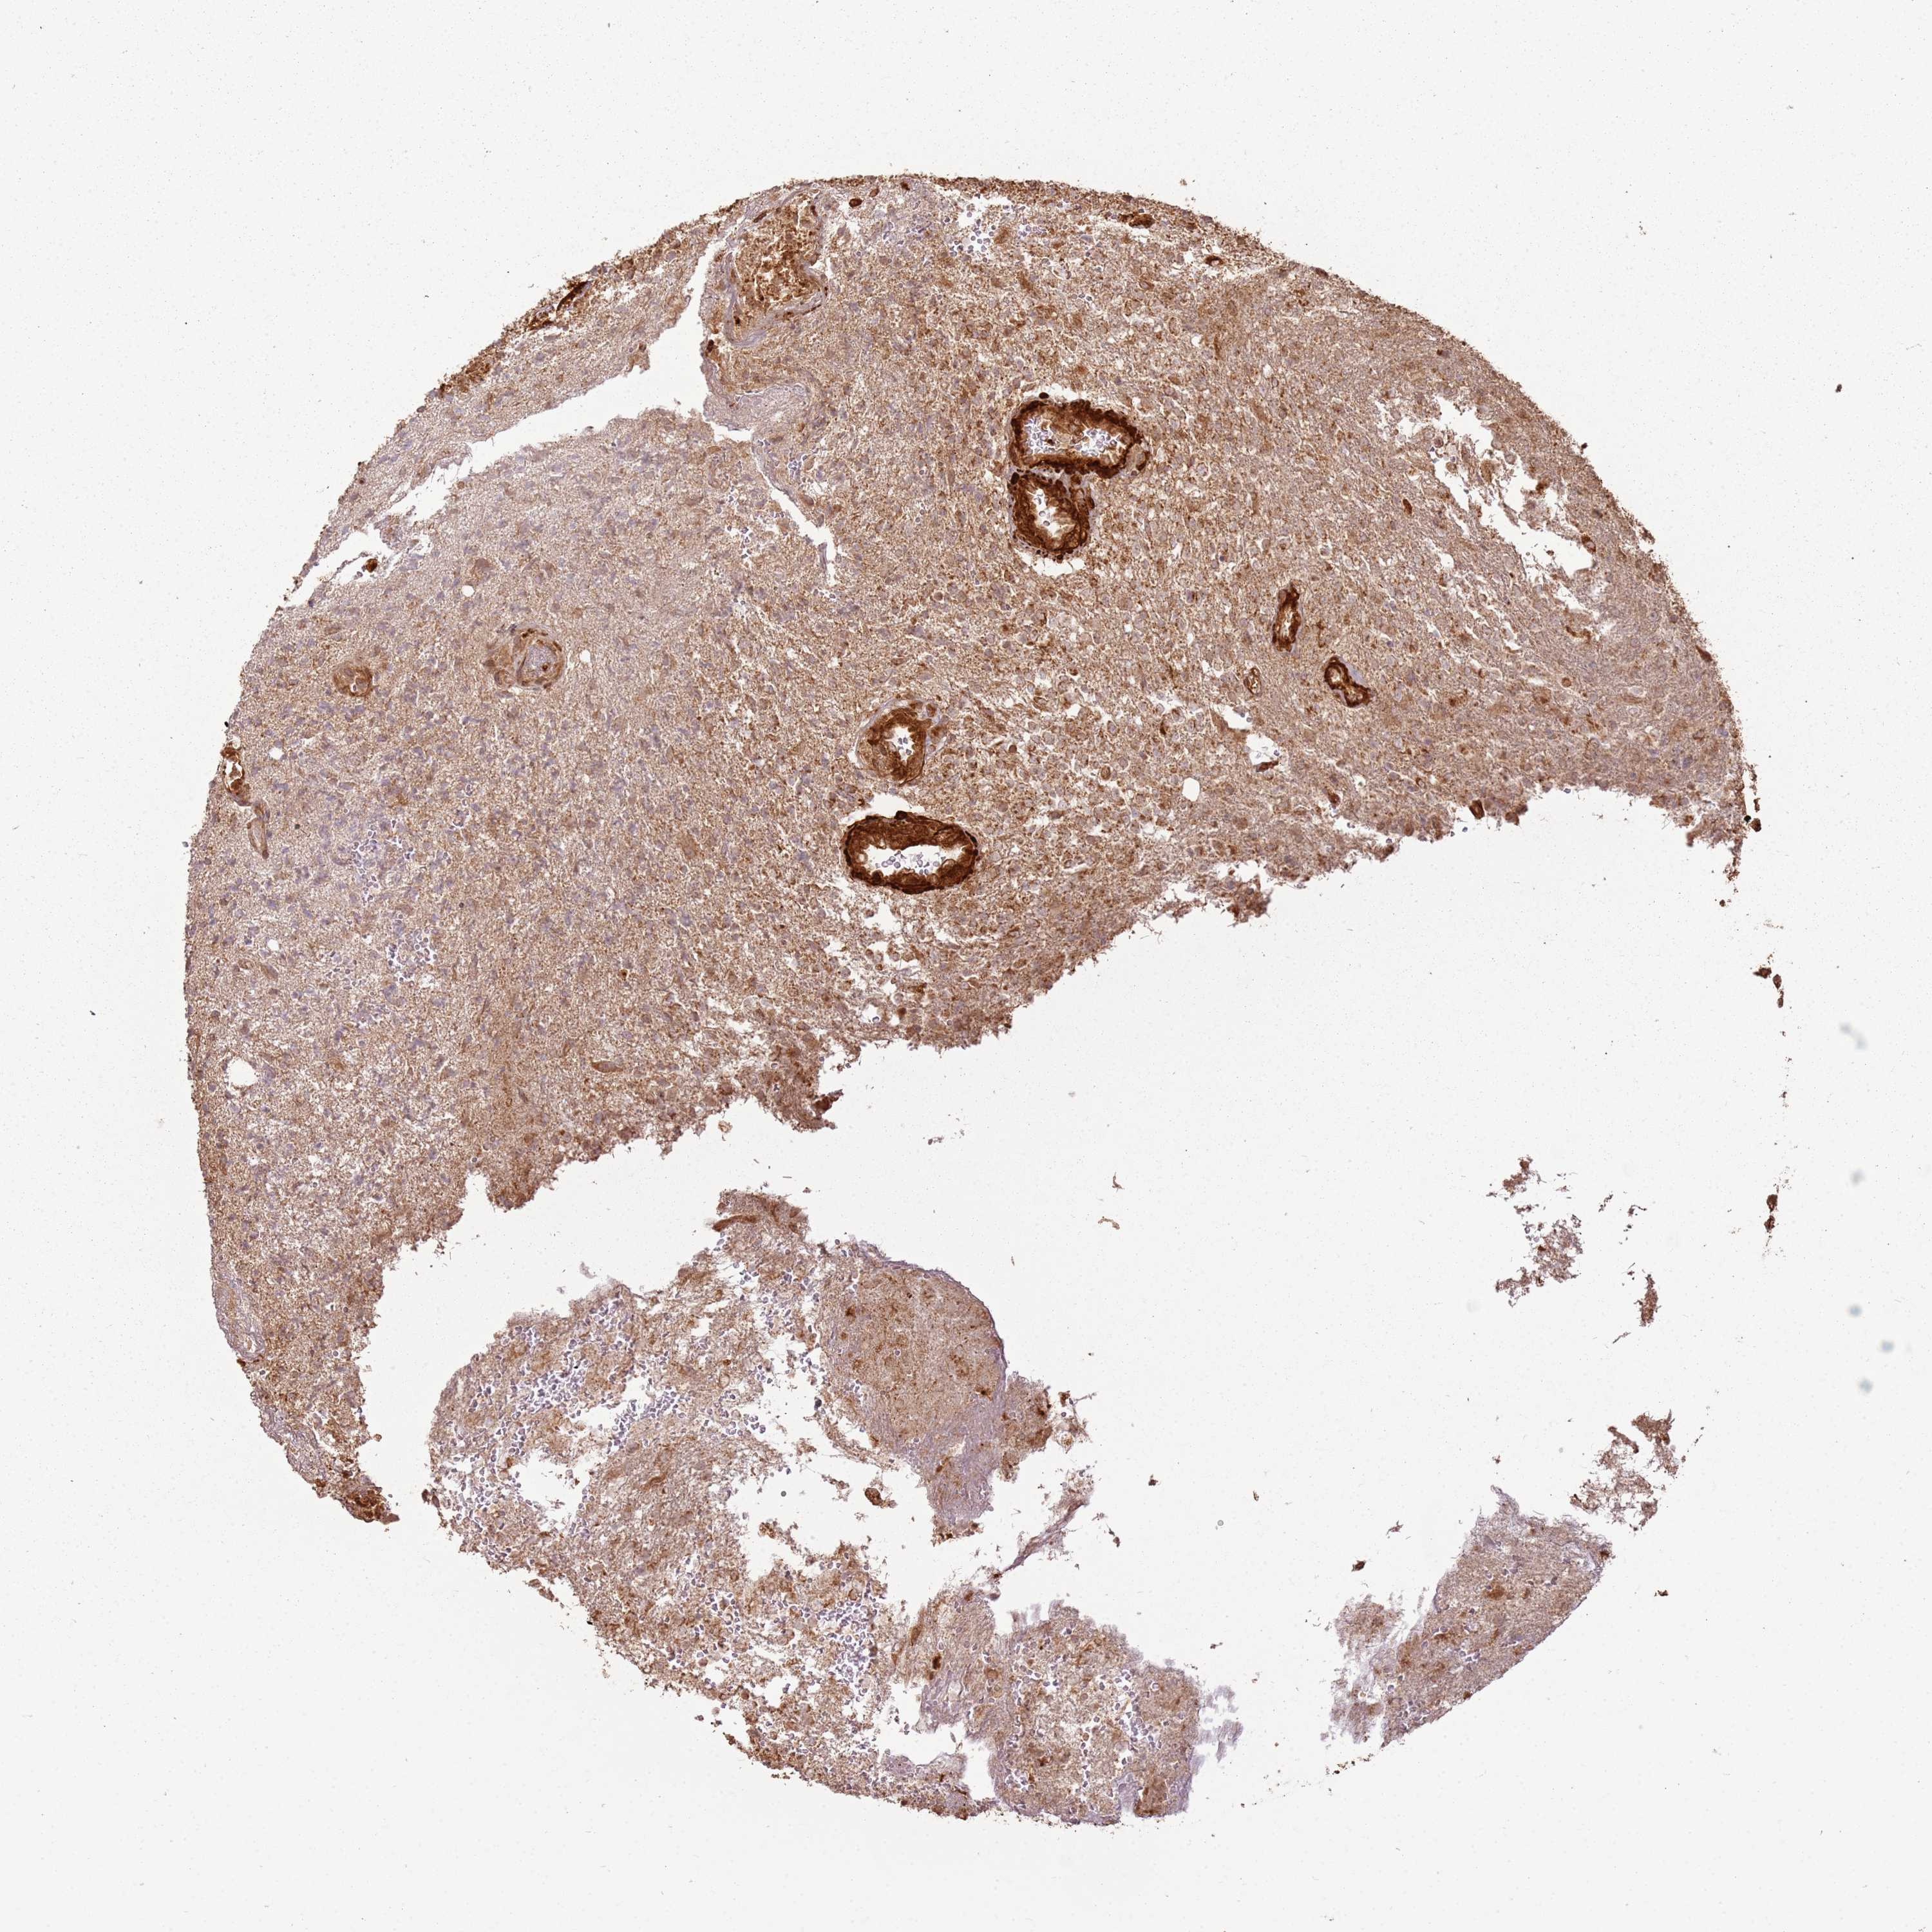

GLIOMA - Protein expressioni

A mouse-over function shows sample information and annotation data. Click on an image to view it in a full screen mode. Samples can be filtered based on level of antibody staining by selecting one or several of the following categories: high, medium, low and not detected. The assay and annotation is described here.

Note that samples used for immunohistochemistry by the Human Protein Atlas do not correspond to samples in the TCGA dataset.

Antibody stainingi

Antibody staining in the annotated cell types in the current human tissue is reported as not detected, low, medium, or high, based on conventional immunohistochemistry profiling in selected tissues. This score is based on the combination of the staining intensity and fraction of stained cells.

Each image is clickable and will lead to virtual microscopy that enables deeper exploration of all samples and also displays staining intensity scores, fraction scores and subcellular localization as well as patient and tissue information for each sample.

Antibody HPA047166

Staining

High

Medium

Low

Not detected

Intensity

Strong

Moderate

Weak

Negative

Quantity

>75%

75%-25%

<25%

None

Location

Nuclear

Cytoplasmic/membranous

Cytoplasmic/membranous,nuclear

Glioma, malignant, High grade

Glioma, malignant, Low grade